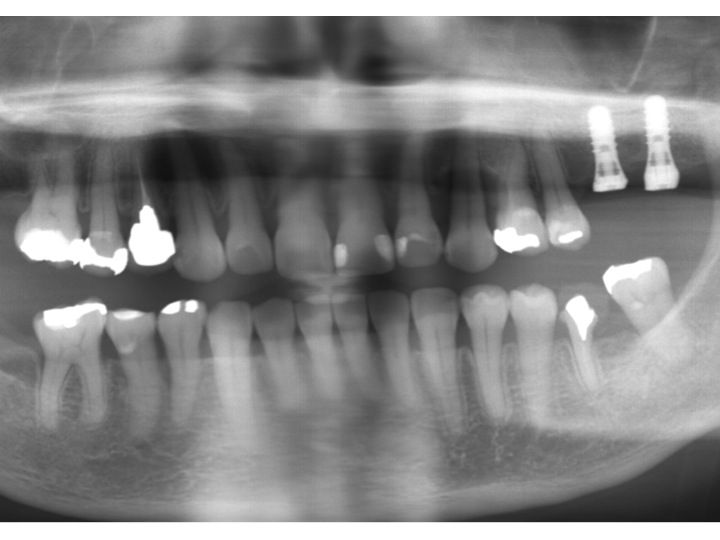

それではインプラントのブログになります。

最近行なった手術後のレントゲンのみアップします。

上の症例は、奥歯に骨の高さが非常に少なかったので、

ソケットリフト法という治療を行い、

十分な長さのインプラントを埋め込みました。

上の症例は、

骨吸収は多少ありましたが、十分な長さのインプラントを2本埋め込むことが可能でした。

比較的簡単な手術でした。

上記の症例の方は、下顎の左右奥歯が欠損しているが、

費用的な問題もあり、

片側に1本のインプラントを行なったケースです。

たった1本のインプラントでもこの部分で噛めるようになることで、

食生活も大きく変わりますし、

残っている歯への負担も軽減します。

最小限ではありますが、

有効なインプラント治療法と言えます。

上記の方は、以前他歯科医院でインプラント治療経験がある方です。

当医院では追加で2本のインプラントを行ないました。

上記の方は、多くの欠損があります。

少しでも早く噛めるようになるために、

短期的にインプラント手術も行なった方が良いケースです。

また、この方は噛み合わせに大きく問題があるため、

インプラント以外にも治療が必要なことろが多くあります。

こうした方の場合、インプラント手術後に骨としっかりとくっつくまでの期間を利用して

治療を進めることで、効率的な治療が行なえます。

上記の症例の方は、

一見すると単に2本のインプラントを行なっただけと思われるようなケースですが、

非常に難易度が高い症例です。

その理由として、骨吸収が非常に大きく難しい手術だったのです。

骨の幅は、理想的な幅の30%程度しかなく、

骨の高さも非常に少ない状態でした。

下顎の奥歯の場合、下顎神経というのがあり、

その部分に触れないようにギリギリの位置で

インプラントを埋め込みました。

本日紹介するインプラント手術の中では最も難易度の高いオペでした。

上記のケースは最も簡単なインプラント手術の一つでした。

多少の骨吸収はありましたが、長さも十分ありしたので、

手術時間も10分もかからず終わったケースです。